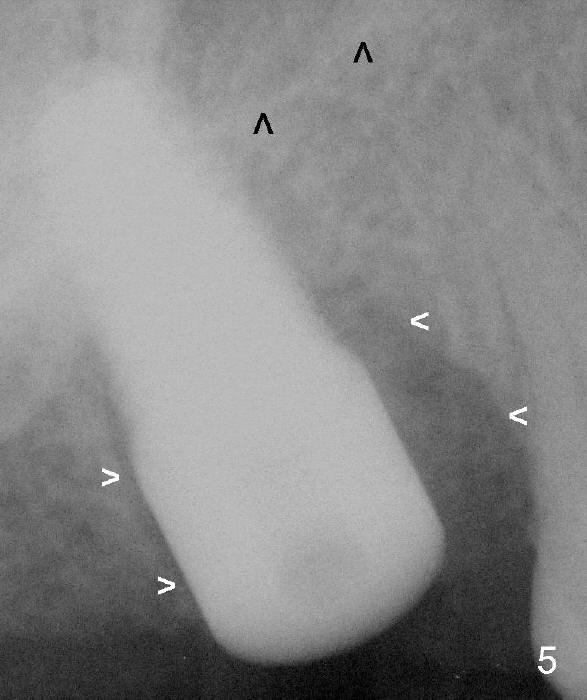

Fig.5 is an immediately postop PA, showing that a 7x17 mm tapered implant has penetrated the sinus floor (black arrowheads). The insertion torque is 40 Ncm. Later the torque increases to 60 Ncm when the implant is placed higher. White arrowheads: mesial and distal socket walls.